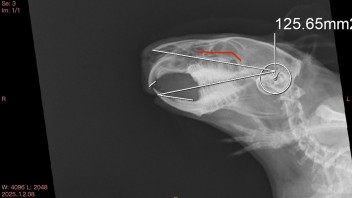

Der Termin beim Heimtierarzt hat dann aber Aufschluss gebracht. Auf einem Röntgenbild des Kopfes konnte man erkennen, dass Emma eine leichte Zahnanomalie hat. Ihre linken Backenzahnwurzeln sind scheinbar minimal zu lang. Der Arzt meinte, es sei nicht auszuschließen, dass sie in Zukunft ein Zahnschweinchen werden kann. Wenn sie in ein paar Monaten ausgewachsen ist, werden nochmal Röntgenbilder angefertigt, um zu sehen wie sich die Situation entwickelt.

Bin schon am überlegen, mir die Röntgenbilder zuschicken zu lassen und noch eine Zweitmeinung einzuholen. Oder sie vielleicht sogar einmal hier im Forum zu zeigen, falls jemand damit Erfahrung hat?

Ansonsten meinte der Arzt, dass es keine gravierende Anomalie sei. Schlimm wäre es wohl erst, wenn sich Entzündungszeichen zeigen würden. Beim Blick ins Maul konnte er wohl nur eine sehr leichte Asymmetrie erkennen